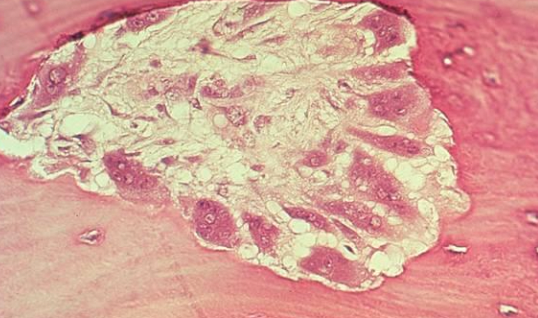

A

Multiple Myeloma with malignant proliferation of plasma cells